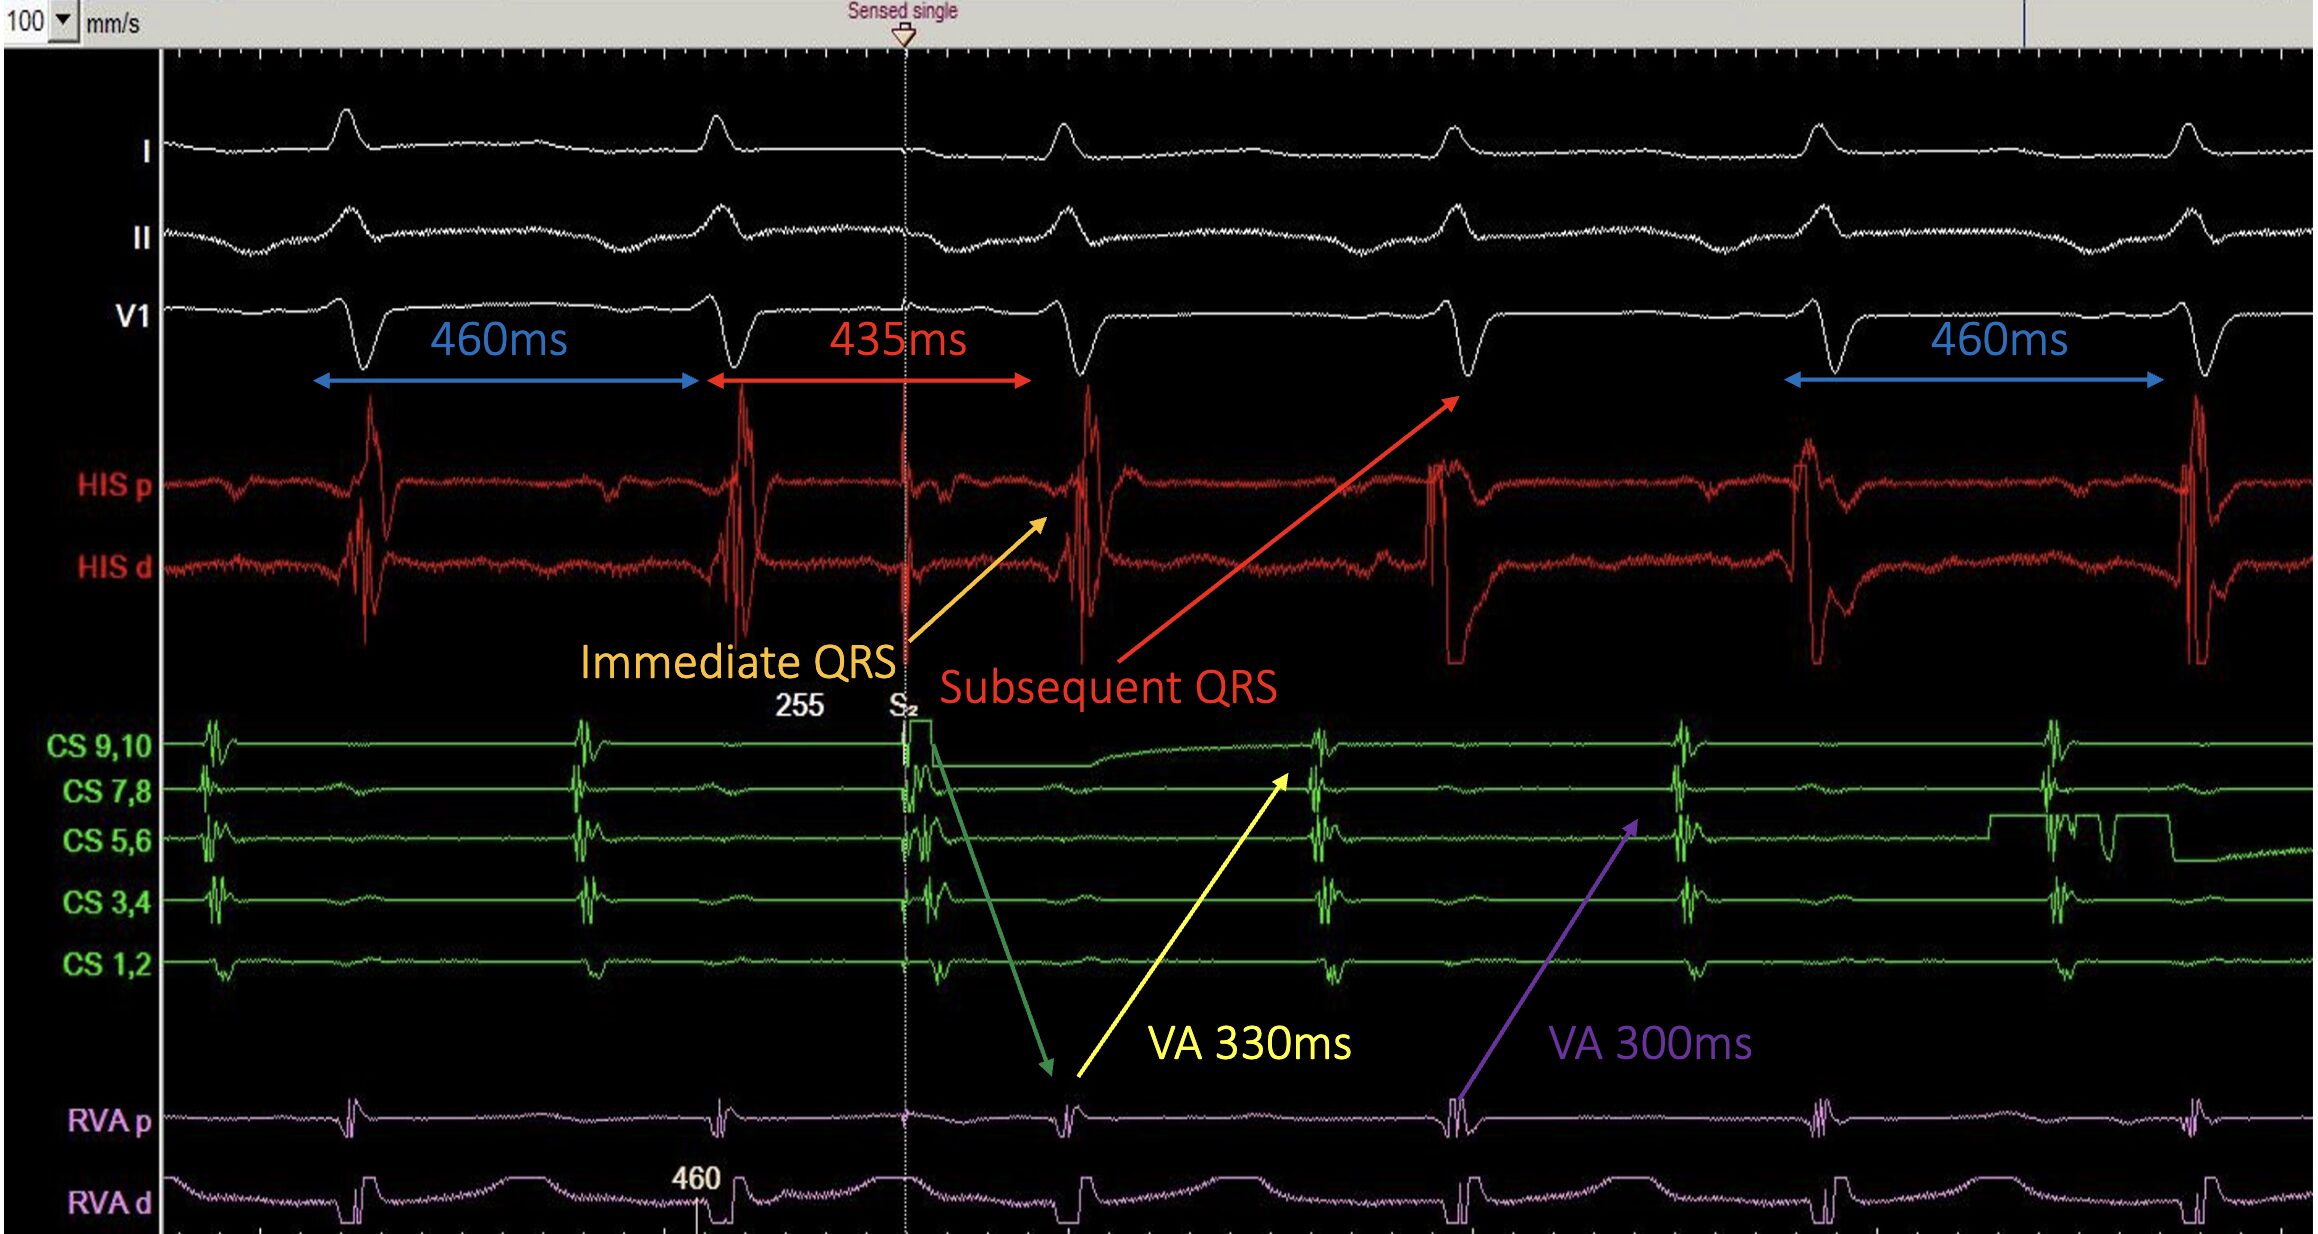

In this example, a sensed PAC is delivered during a long RP tachycardia with inverted P waves in lead II suggesting a low to high atrial activation. The atrial activation shows CS 7-8 earliest followed by CS 9-10 then His A.

The PAC advances the immediate QRS from 460ms to 435ms (we’re using QRS as a surrogate because the His isn’t clearly seen). Advancing of the immediate His/QRS can occur in atypical AVNRT, AVRT, and focal AT so the advancement itself isn’t the discriminator. It simply means the response diagnostic.

- Return VA post-PAC = 330ms (yellow arrow)

- VA during SVT = 300ms (purple arrow)

The VA is Not hooked.